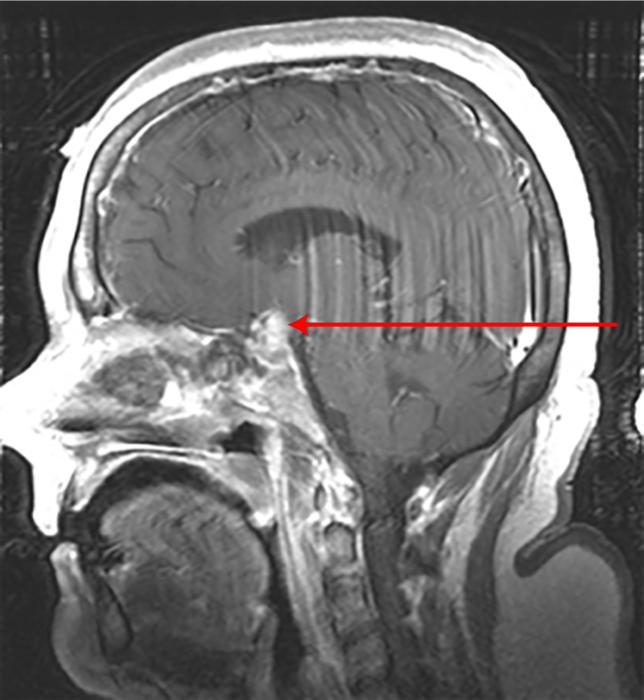

Craniofaringioma: ressonância nuclear magnética (RNM) sagital pós-contraste

Do acervo de Marc C. Chamberlain; usado com permissão

Do acervo de Marc C. Chamberlain